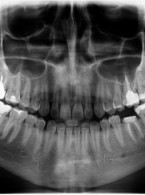

Leczenie agresywnego zapalenia przyzębia u pacjenta z toczniem rumieniowatym układowym: Opis przypadku z 8-letnią obserwacją